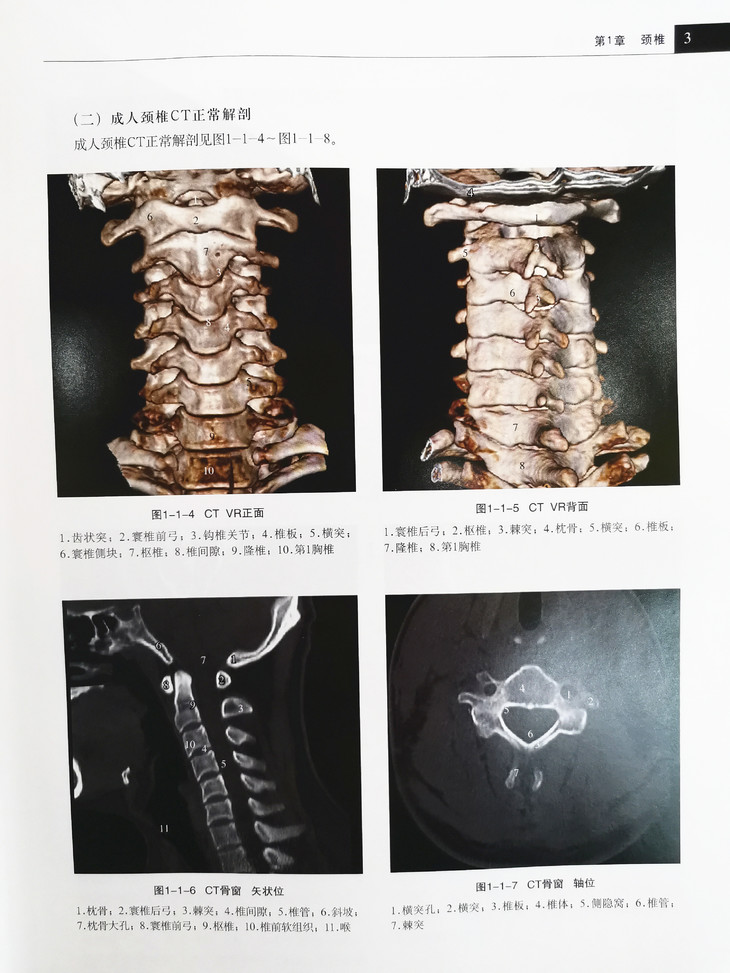

本书从法医学实际工作出发,精选X线图、CT图、MR图近600幅,分3章(颈椎、胸腰椎、骶尾椎)对脊柱损伤的影像学判断进行了详细阐述。

每章附有正常X线、CT及MR影像学解剖注释,以及脊柱急性创伤性损伤和非急性创伤性改变的X线、CT、MR影像学注释。